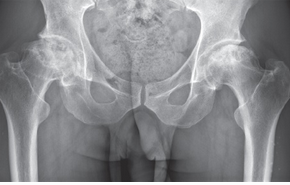

Местный статус при поступлении. Болевой синдром (6 баллов по ВАШ), усиливающийся при активных и пассивных движениях. При ходьбе пользуется тростью, отмечается выраженная хромота. Относительное укорочение левой нижней конечности до 2 см. Гиперемии и припухлости в области левого тазобедренного сустава нет. Местная температура не повышена. Атрофия мышц бедра — 3 см по сравнению с противоположной стороной. Отмечал кратковременный эффект от приема НПВП. На рентгенограммах, КТ и МРТ — признаки асептического некроза головки левой бедренной кости 3B (поздней) стадии по классификации ARCO (рис. 1, 2).

При поступлении визуально припухлости и гиперемии кожных покровов в области тазобедренных суставов не отмечалось. При пальпации — локальная и осевая болезненность в проекции головки правой бедренной кости. Объем движений в правом тазобедренном суставе ограничен — наружное отведение 10°. Боль по ВАШ 5–6 баллов. Левый тазобедренный сустав безболезненный, движения в нем в полном объеме. Укорочение правой нижней конечности на 2,0 см. На рентгенограммах и КТ — признаки двухстороннего асептического некроза головок бедренных костей, больше выражены справа — 3В стадия по ARCO (рис. 4, 5). В анализах крови отмечается ускорение СОЭ до 58 мм/ч., остальные результаты — в пределах референсных значений.

Рис. 4. Клинический случай 2. КТ таза, реконструкция в аксиальной проекции — двусторонний некроз головок бедренных костей: справа — 3В (поздняя) стадия по ARCO, слева — 3А (ранняя) стадия по ARCO

Рис. 5. Клинический случай 2. Рентгенограмма во фронтальной проекции — двусторонний асептический некроз головок бедренных костей: справа — 3В (поздняя) стадия по ARCO